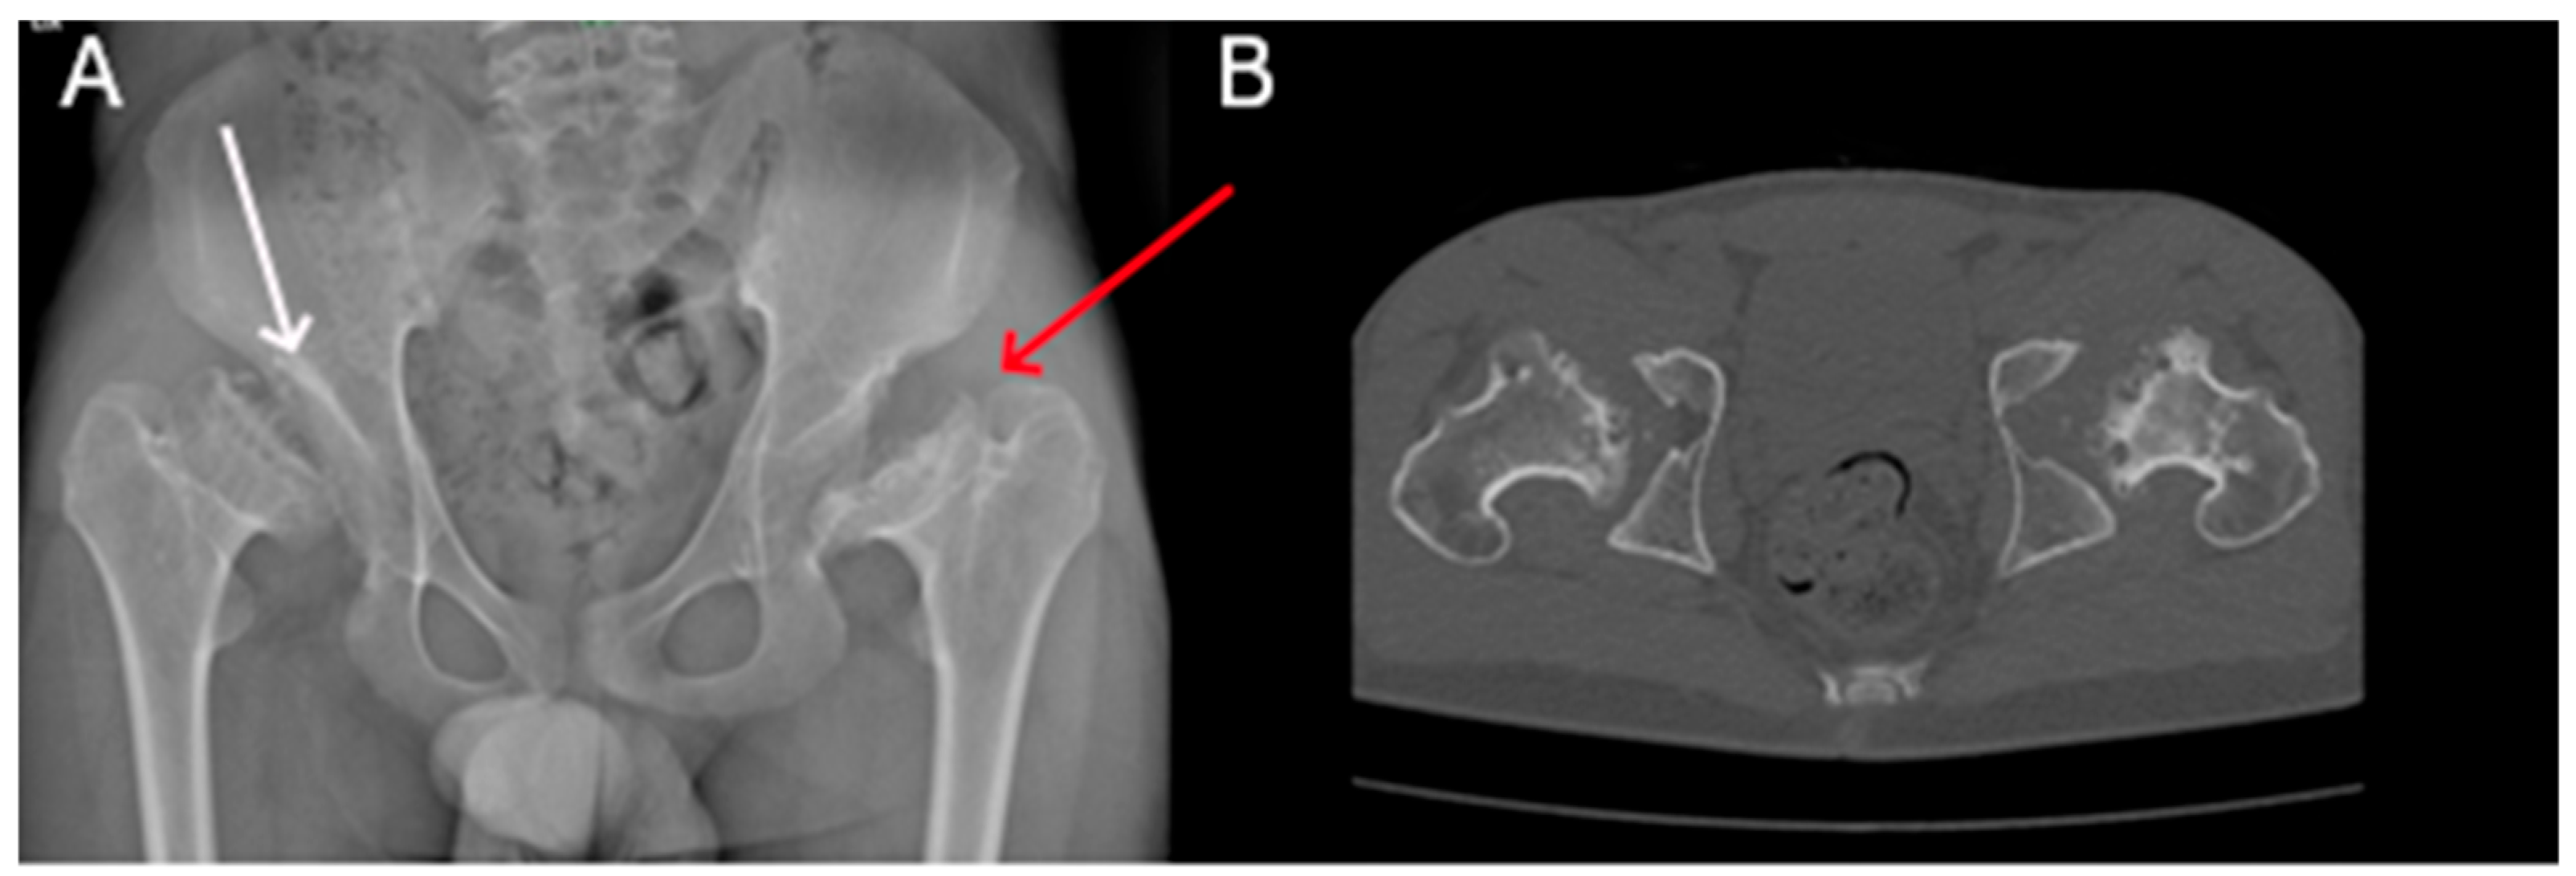

| Hip dysplasia | + | + | + | + | + | + | + | + |

| Dysmorphic long bones | + | + | + | + | + | + | ||

| P1 (MPSI) | Baseline | RX | Pelvis | Mild iliac wing hypoplasia; shifty acetabular roofs. |

| After 3 years of ERT | RX | Pelvis | Thickening of the acetabular roofs. | |